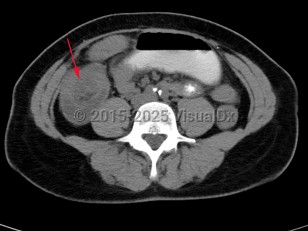

Intussusception is a telescoping or invagination of a part of the intestine into the lumen of an adjacent segment. Intussusception can present with variable severity. It can present with bowel ischemia and perforation with need for emergent surgical intervention, or it can present as relaxing / remitting abdominal pain of unclear etiology with intermittent symptoms and no signs of systemic illness. Jejunojejunal, jejunoileal, ileoileal, ileocolonic, and colocolonic are all types of intussusception that can occur, with the majority involving the small intestine.

Initial management requires ensuring hemodynamic stability, as many patients are dehydrated, and assessing concern for bowel perforation, which could require broad-spectrum antibiotics and urgent surgical intervention. Air or barium enemas can be both diagnostic and therapeutic. However, intussusception will frequently recur, in which case surgical resection is often required. Further imaging (ie, small bowel x-ray series, CT or MRI abdomen) can be utilized to identify the etiology if it is unknown based on presenting symptoms and a barium / air enema.

Initial management requires ensuring hemodynamic stability, as many patients are dehydrated, and assessing concern for bowel perforation, which could require broad-spectrum antibiotics and urgent surgical intervention. Air or barium enemas can be both diagnostic and therapeutic. However, intussusception will frequently recur, in which case surgical resection is often required. Further imaging (ie, small bowel x-ray series, CT or MRI abdomen) can be utilized to identify the etiology if it is unknown based on presenting symptoms and a barium / air enema.